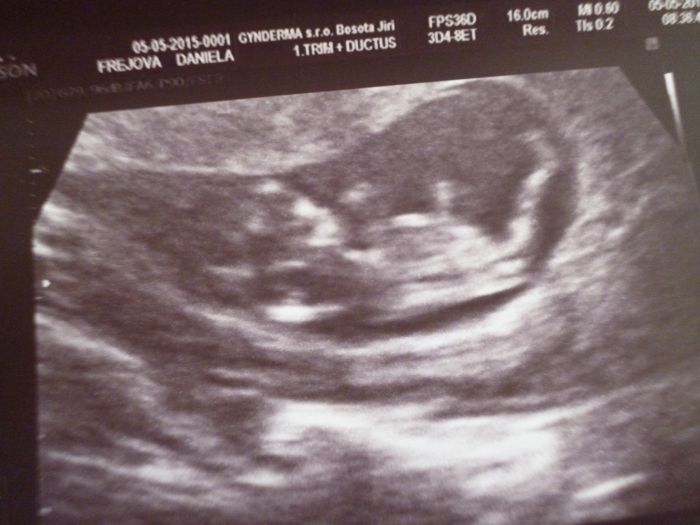

Ahojte holky,

tak my uz jsme poscreeningu. Mimco vypada v poradku, jeste bylo brzy aby bylo videt co to bude.

Danko,moc hezká fotečka:-).